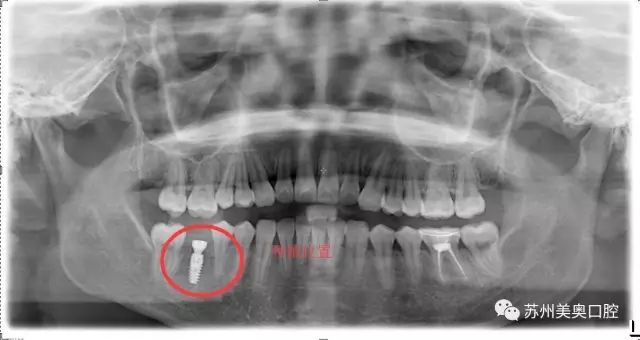

光学显微镜主要用于放大微小物体成为人的肉眼所能看到的仪器,所以被广泛应用于医学研究和临床手术中。口腔显微种植高精度可以精确到1毫米,将细微的口腔解剖结构放大近30倍,患者看到的下图仅仅放大了10倍。

相比于传统肉眼观察,显微口腔治疗为医生提供了聚焦光源和放大的清晰视野,明确分辨微小的神经血管,便于医生更换更小更精密的工具,进行的治疗,让种植牙更加安全高精。苏州美奥显微口腔治疗利用现代医疗科技一步一步实现着口腔治疗微观高精化。

我很久之前就想把牙齿种起来,只是担心牙槽骨那里已经很狭窄了,再加进一颗钉子会不会很不安全。直到看到美奥口腔的显微种植,术区可以放大到30倍,口腔视野很清晰,觉得种植很安全,所以才决定进行显微种植牙治疗。”

显微种植牙的优势在于口腔组织结构被放大,原本需要切口甚至翻瓣进行观察处理炎症的地方,只需很小的切口,就可看清,继而进行操作;

利用显微放大操作,医生可更换更小工具,利用更细的缝合线等,从而操作更加高高精创,减少了损伤,术后不适降低,恢复更快。

林小姐手术仅十分钟就已完成,术后表示无痛感,显微种植也让大家对种植技术有了进一步的认识。